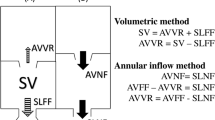

Multiple comparisons were made in this study. Our primary objective was to measure pulmonary net flow as a surrogate for pulmonary regurgitation. Pulmonary net flow, calculated as pulmonary forward flow (FF) minus regurgitant flow, was compared to aortic net flow (ANF) of the same patient as a reference standard for stroke volume (SV). With perfect accuracy, there would be no difference between PNF and ANF since all patients were without shunt lesions. We compared 2D ANF to 2D PNF measured at the PV, and 4DF ANF to PNF measured at the PV, MPA, and BPAs, respectively. Accuracy of semilunar FF was compared to SV of the respective ventricle by volumetry as a measure of internal consistency. Of note, patients with tricuspid regurgitation ≥ 5% (n = 3, range 10–21%) as measured by CMR were excluded from the analyses comparing RV SV to pulmonary FF. Tricuspid regurgitation was calculated by directly measuring the regurgitant jet by 4DF as per our institutional standard practice [32]. To further study utility of 4DF CMR, we directly compared PNF and PR measurements by 4DF and 2D CMR given their clinical importance in the rTOF population. PR was calculated as ((pulmonary FF-PNF)/PNF)*100 and considered mild if < 20%, moderate if 20–40%, and severe if > 40% [33].

Our secondary objective was to assess accuracy of 4DF CMR to measure ventricular size and function compared to 2D CMR. Volumes were indexed to body surface area, calculated using the Haycock formula [34]. Stroke volume (SV) was calculated as EDV-ESV for each respective ventricle. Ejection fraction (EF) was calculated as ((EDV-ESV)/EDV) × 100.